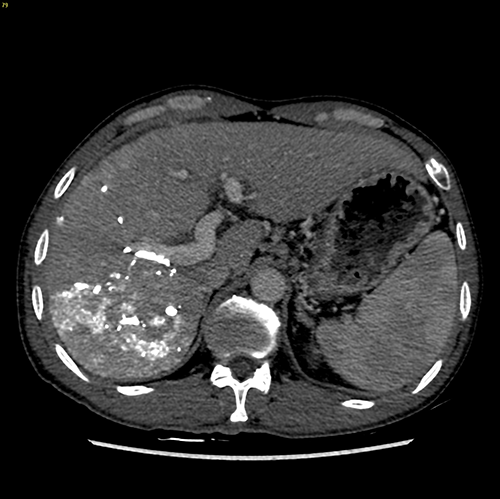

右肝癌---右三肝切除

介入后2周